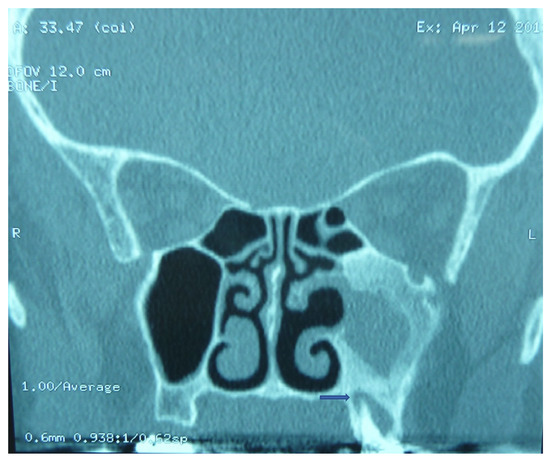

3. Presentation

4. Management